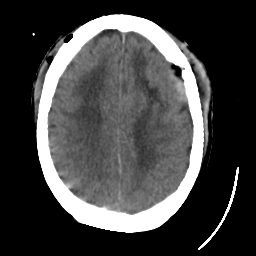

Meningioma: Roentgen-ray CT #1 -- Slice #15

[Home][Help][Clinical] Slice 15